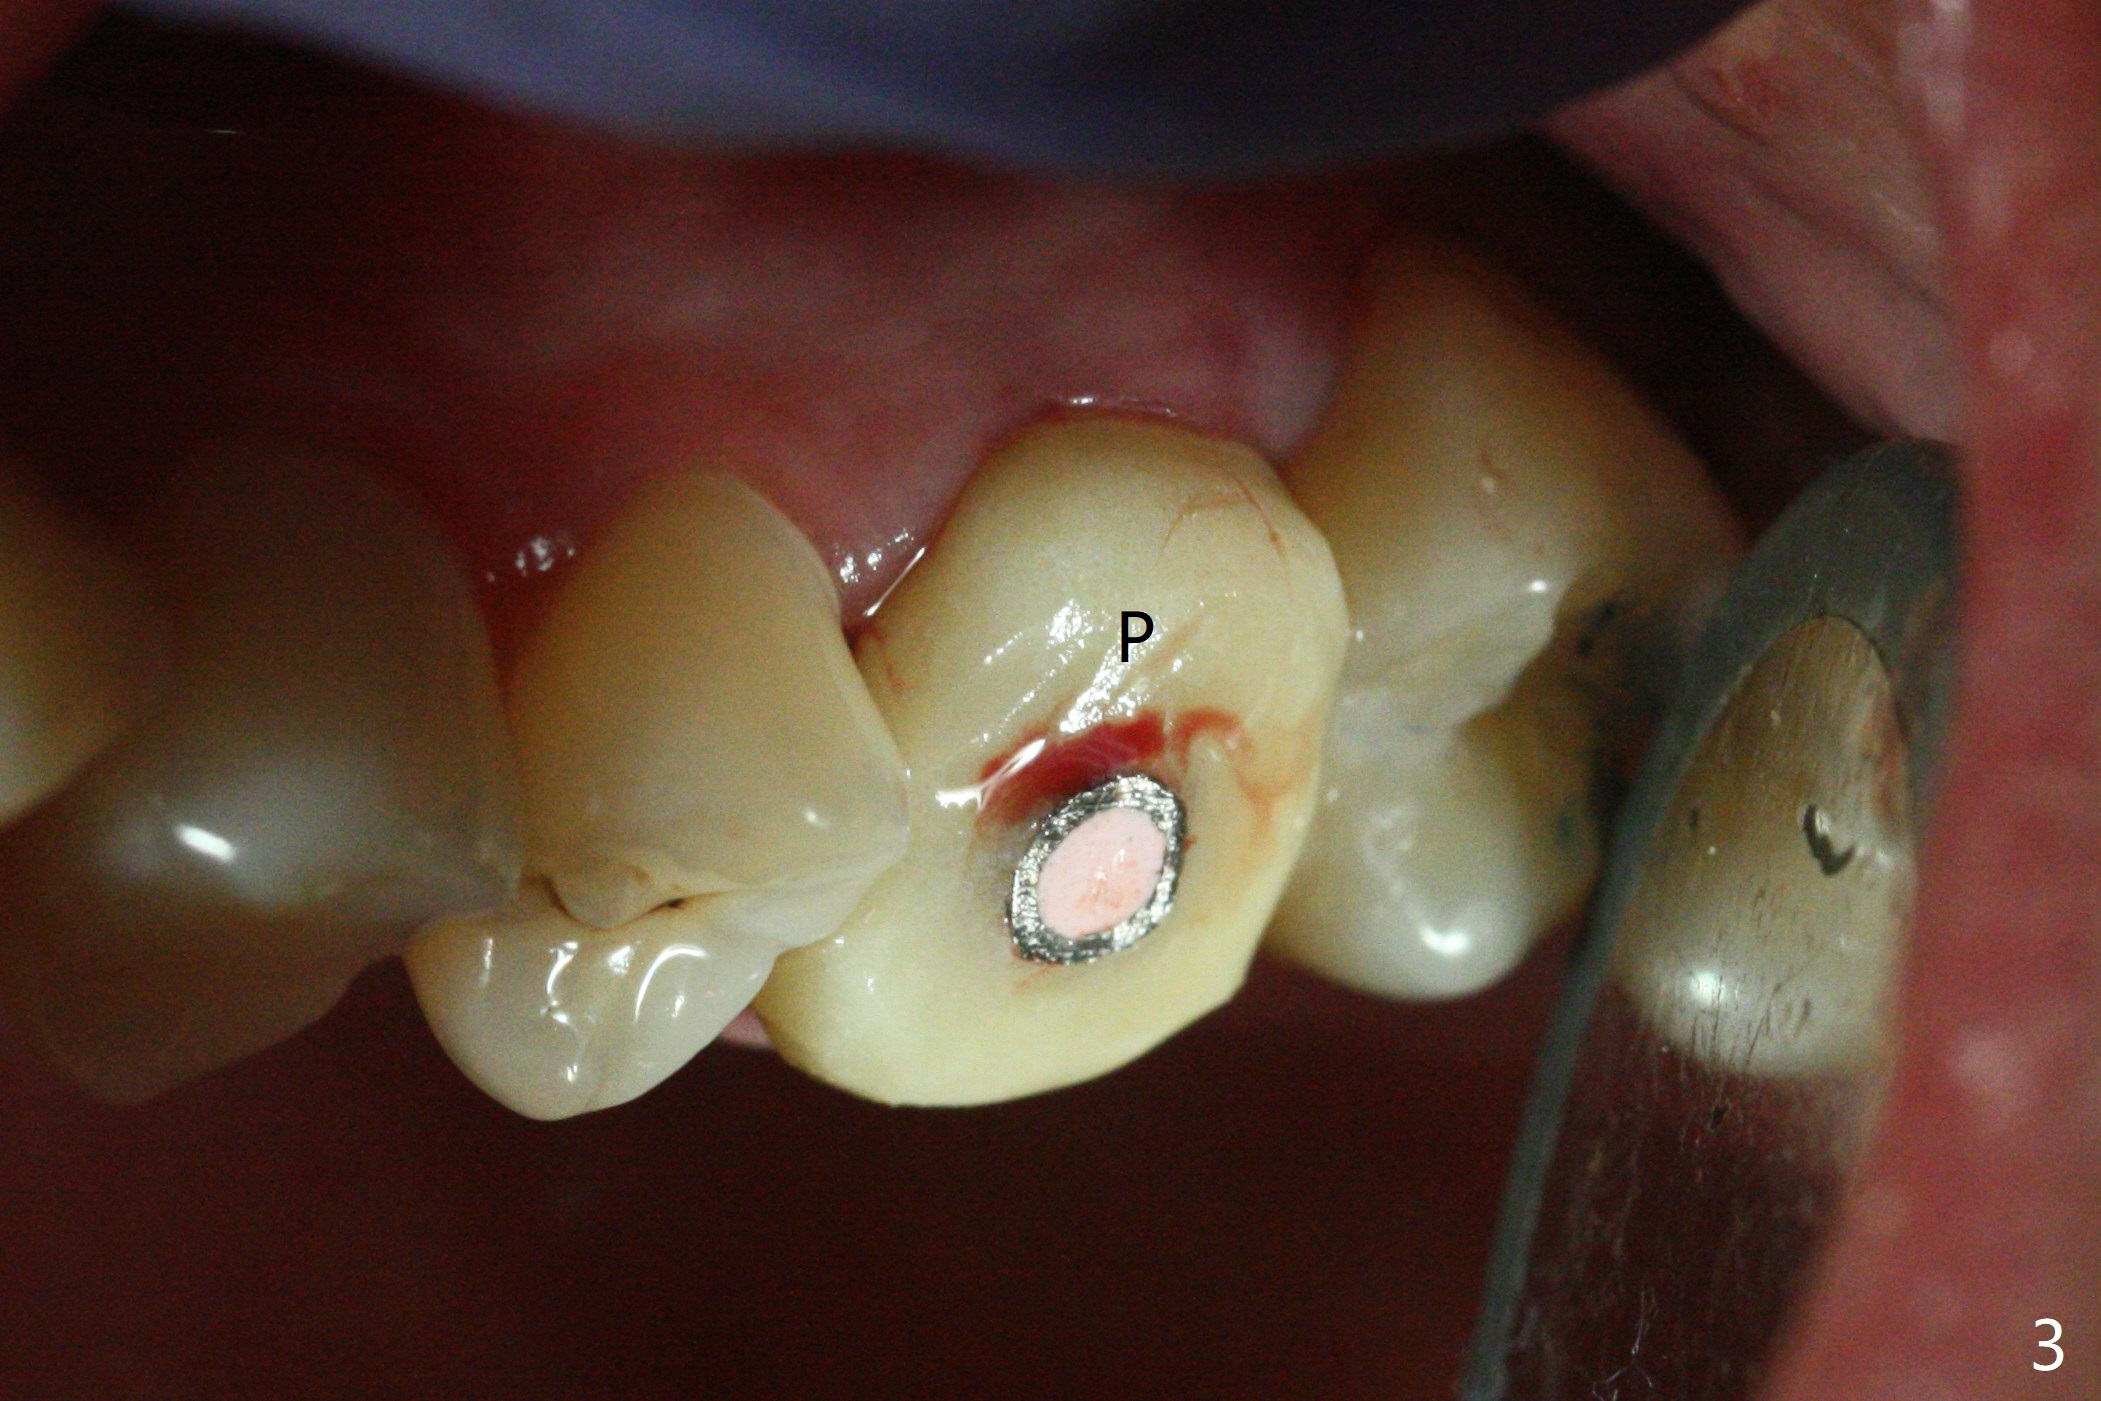

When a 4.5x10 mm implant is placed with sinus lift at #14 (Fig.1), a 5.2x8(2) mm temporary abutment is inserted with height adjustment. Advantage is that an immediate provisional (Fig.2 yellow lines; Fig.3 P) has an ideal emergency profile so that there is less chance of food impaction associated with the future permanent crown. It appears that the mesial portion of bone graft in the mesial gap has been converted to the native bone (lamellar) in 3 months (Fig.4). Bone graft appears to be integrated to the native bone and the implant 14 months postop (Fig.5).